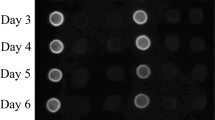

In E. coli, the OPS is transferred to lipid A by the WaaL enzyme to produce LPS. To effectively conjugate the OPS on a protein by PglB, the waaL gene was deleted from E. coli O86 using a λ-Red recombination system. The waaL gene deletion was confirmed using test primer pair t-waaL-F/t-waaL-R, which could amplify across the deletion area. Furthermore, ladder straps were observed on the SDS-PAGE gel of LPS from wild E. coli O86, while no straps were observed in the lane of the LPS extracted from E. coli O86 ΔwaaL, which indicated that the LPS of E. coli O86 ΔwaaL had a low degree of polymerization (Fig. 3). Therefore, we successfully obtained a strain of E. coli O86:B7 without the waaL gene.